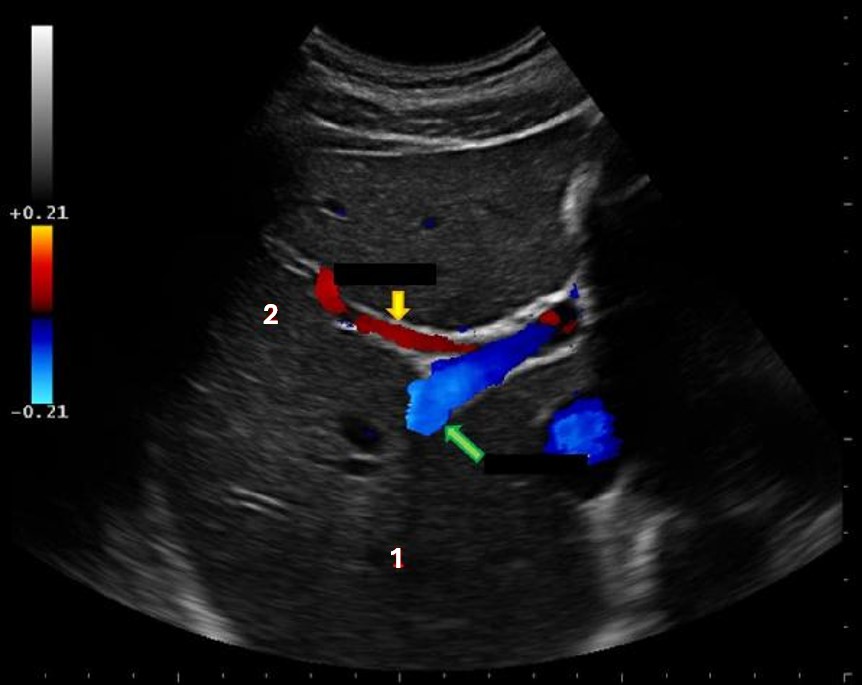

Which of the following structures is labeled #2?

gastroduodenal artery |

What structure is indicated by the blue arrow?

right portal vein |

What structure is indicated by the green arrow?

Main portal vein |

What structure is indicated by the red arrow?

|